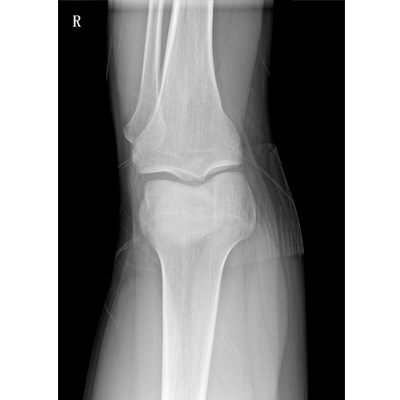

Clinical picture

臨床圖片